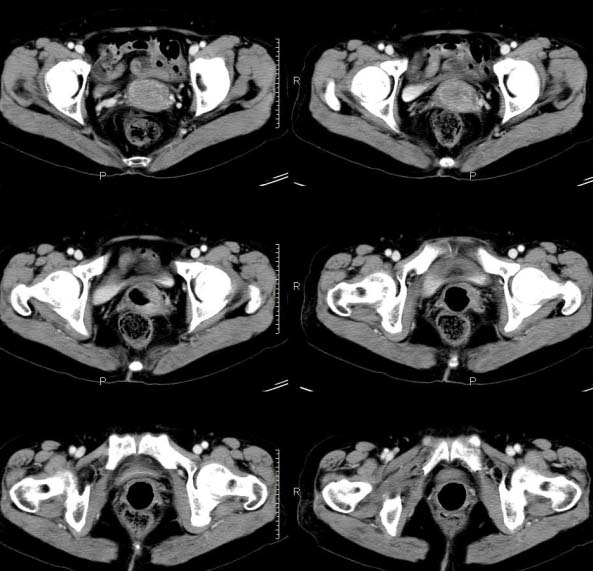

女,63岁,绝经15年,从阴道内有液体流出约1月余,且带有血,患者一般情况很差,在家属搀扶下行走。请大家看看是子宫病变还是宫颈病变?

子宫颈体积增大,宫颈壁不均匀性增厚,且不均匀性强化。考虑为宫颈ca。

子宫颈内见低密度影,外形不规则,不均匀强化,考虑占位,子宫颈癌可能性大。